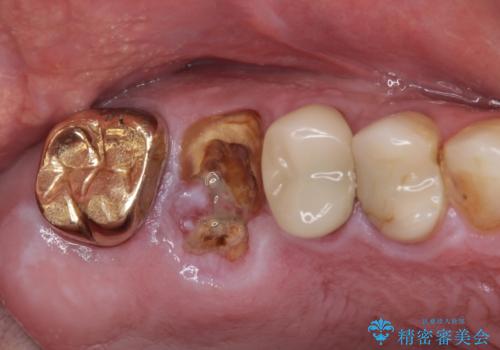

- 咬んだときに奥歯に痛みを感じるとのことで来院された患者様です。

診査の結果、左側は奥歯2本、右側は1本の抜歯が必要であることが分かりました。

左側は大臼歯2本と小臼歯1本が欠損しているため、インプラント2本を治療したブリッジ、右側は中間欠損であり、前後の歯も加療が必要であったためブリッジによる補綴治療を行うこととしました。

抜歯となった歯は全て神経が抜かれた歯であり、強大な咬合力によって破折したことが原因で抜歯となりました。

左右同時に強大な力を受けながらの治療であったため、仮歯の脱落や破損などがひんぱつしました。